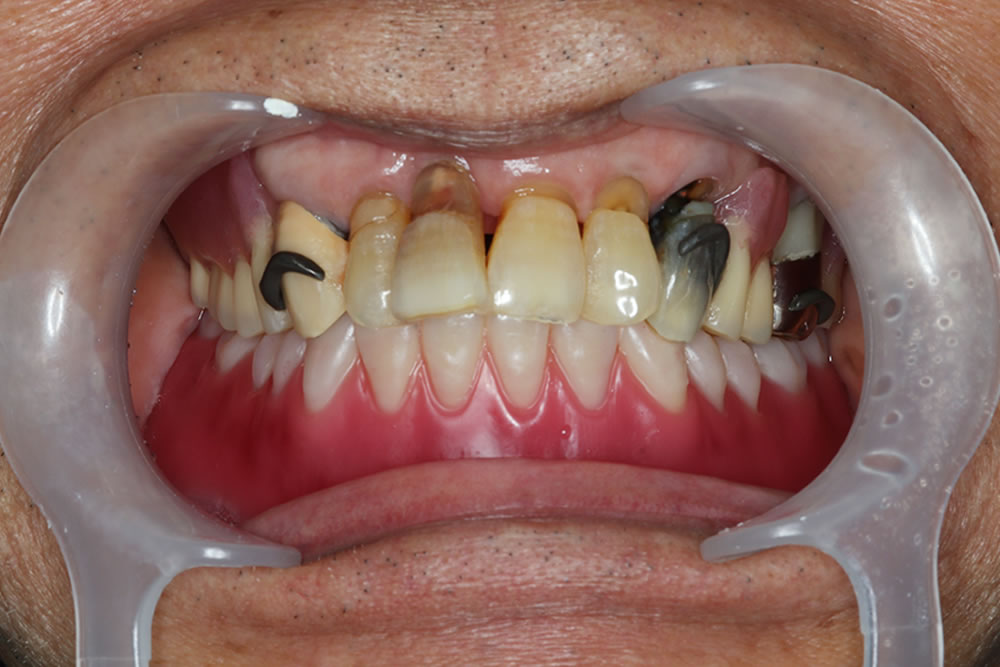

コピーデンチャーを用いて下顎総義歯を作り変えた症例

こちらの患者さまは、他院で総義歯を作製したものの「噛めない」「外れやすい」という状態が続き、入れ歯の作り直しを希望され来院されました。特に下顎の義歯が安定せず、日常生活にも支障が出ていたとのことです。

初診時のお口の状態

診察したところ、下顎の顎堤吸収(入れ歯を支える歯槽骨が痩せてしまう状態)が進行し、顎の骨の高さが全体的に低くなっていました。このような顎堤の形態では、通常の総義歯は吸着が得られにくく、義歯の安定が非常に難しい症例となります。

前歯以外の歯は目立たないこともあり、そのままで放置されている方も多いように感じます。しかし、歯を長期間抜けた状態にしておくと、少しずつ歯が移動して歯並びや咬み合わせが悪くなり、咬み合わせが元に戻らない「咬合崩壊」の状態になってしまいます。咬合崩壊の状態になると、治療が困難となったり、行えた場合であっても時間と費用がかかってしまうため、できるだけ早めの治療をおすすめします。症状によっては、入れ歯以外の治療法などもご提案可能ですので、ぜひ一度ご相談ください。